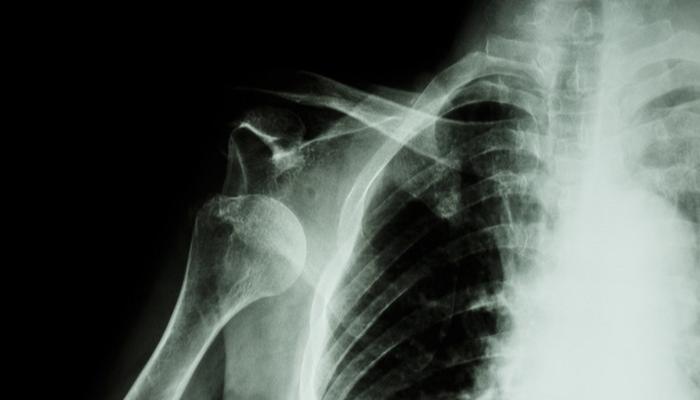

肩关节脱位按肱骨头脱出的方向可分为前脱位、后脱位、盂肱关节下脱位及上脱位四种类型。其中,肩关节前脱位是临床上最常见的脱位类型,约占肩关节脱位的95%以上。肩关节前脱位又可分为喙突下脱位、盂下脱位、锁骨下脱位和胸腔内脱位四种。